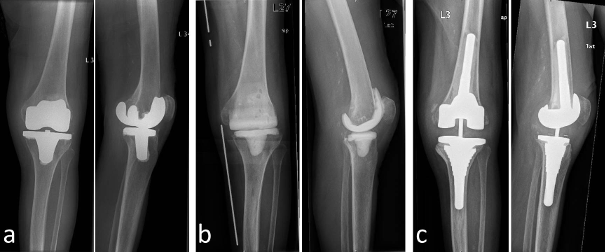

In this retrospective study, we included patients who were treated in our clinic between 2005 and 2013 due to infection of the knee after total knee arthroplasty. We excluded all patients with an intramedullary cement spacer, patients who were finally treated by performing arthrodesis of the knee and all patients who could not be followed up for at least 6 months. All patients included have had a mobile antibiotic-coated cement spacer (AGC Style Company Biomet Orthopedics Inc., Warsaw, USA) implanted after surgical debridement and removal of the components of total knee replacement. The mobile cement spacer consists of a femoral component and a tibial component (each filled with 80 g cement and containing gentamycin and clindamycin) and is adapted to the anatomical condition. Broad-spectrum antibiotics were given initially and in some cases they were replaced by other antibiotics according to resistance. Systemic antibiotic treatment took place over a period of 4–6 weeks. Subsequently, reimplantation of total knee replacement was performed when no clinical or paraclinical signs of infection were found. Prior to reimplantation, a diagnostic puncture of the knee joint was performed in every case to rule out infection. Depending on the bony defect situation and the stability of the collateral ligaments, resurfacing, partially or fully constrained knee replacement was carried out (Figure 1 [Fig. 1]). We analyzed all included cases for potential reinfection, examined the range of motion of the knee joint and evaluated the Merle d’Aubigné-Postel score. Statistical evaluation was performed with SPSS 24.0.

Figure 1: a) X-ray showing TKR with no signs of loosening, yet clinical signs of infection. b) Explantation of the components of TKR and dynamic cement spacer in situ. c) Reimplantation with a semi-constraint TKR.